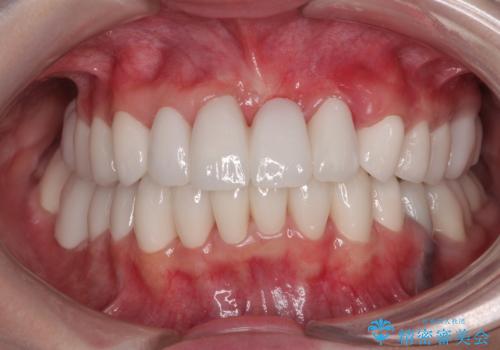

色のバランスの悪い前歯 オールセラミッククラウンで自然な口元に